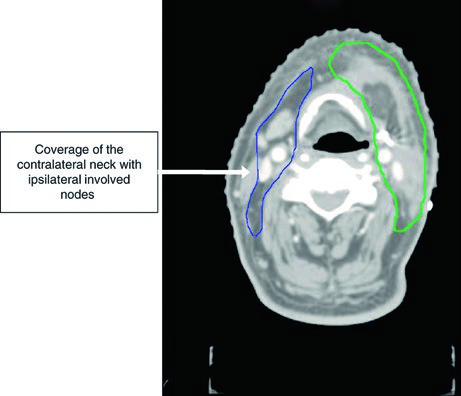

Caso Clínico: Mucosa Yugal T2N3b con Extensión Extranodal

La Figura 6.5 presenta un CEC de mucosa yugal, T2N3b, post-resección con vaciamiento cervical derecho y extensión extranodal en el nivel IB. Márgenes negativos pero próximos en el margen profundo. El CTV66 (rojo) cubre la región ganglionar con extensión extranodal.

El CTV60 incluye el lecho operatorio y toda la mucosa yugal, con niveles I a IV ipsilaterales. El CTV se extiende cranealmente hasta el surco vestíbulo-gingival y fosa infratemporal a la altura del reborde orbitario inferior, caudalmente hasta el surco vestíbulo-gingival y glándula submandibular, anteriormente hasta la comisura labial, y posteriormente hasta el trígono retromolar. Se necesitan márgenes amplios incluso para tumores primarios menores. Se coloca bolus cutáneo para cobertura adecuada de los CTVs de alto e intermedio riesgo.

El CTV54 incluye los niveles I a III contralaterales, debido a la extensión de la enfermedad ganglionar en el cuello ipsilateral. Este caso ilustra cómo la presencia de extensión extranodal amplía significativamente los volúmenes de tratamiento necesarios.